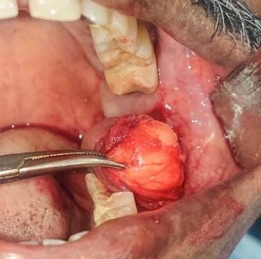

Figure 2

The lesion was surgically removed under local anesthesia. Under standard patient preparation, LA was administered along with peri-tumor anaesthesia. The incision was placed along with the anterior border of lesion and soft tissue dissection was done to separate the lesion from adjacent structures. After the lesion was separated from the underlying structures the lesion is carefully excised preserving the buccal mucosa and the incision site is ; closed with 3-0 braided silk. Sample was sent to histopathological evaluation. Post op instructions given and adequate antibiotics and a nalgesics were prescribed. The patient was recalled after 3 days for review and suture removal done after one week. Healing was uneventful.